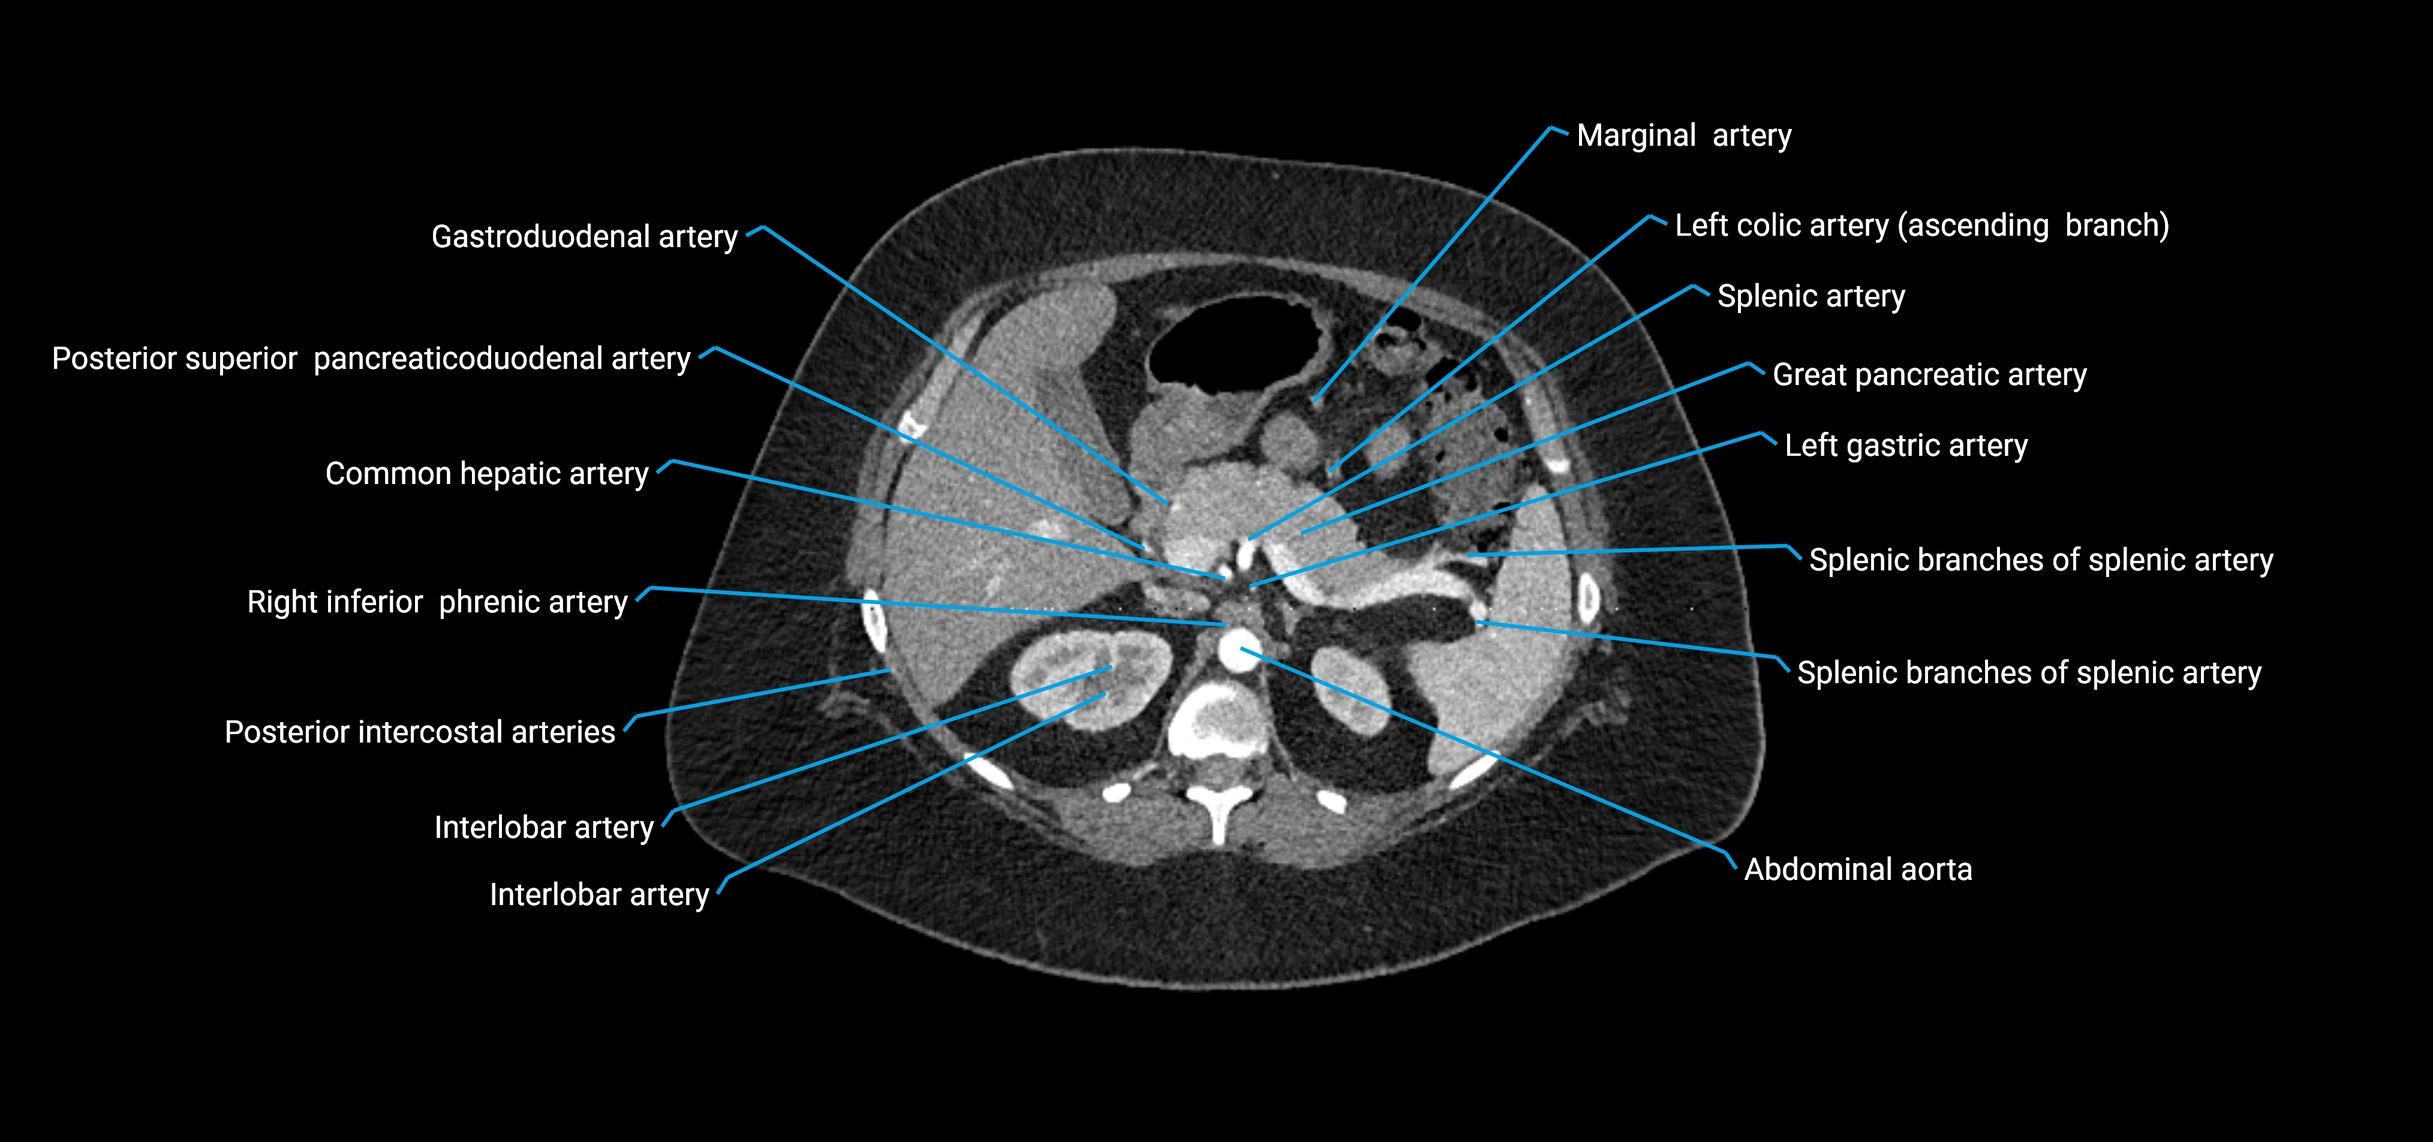

CT Appearance

Non-contrast CT:

• Appears as a tubular soft tissue structure anterior to vertebral bodies

• Calcified atherosclerotic plaques appear as hyperdense foci along the wall

• Useful for screening abdominal aortic aneurysm (AAA) size and mural calcification

Contrast-enhanced CT (CTA):

• Gold standard for abdominal aortic imaging

• Provides excellent detail of lumen, wall, aneurysm, thrombus, and branch vessels

• Multiplanar and 3D reconstructions help in aneurysm measurement, stent graft planning, and dissection evaluation

• Detects acute rupture, traumatic injury, or occlusion with high sensitivity

CT images

image